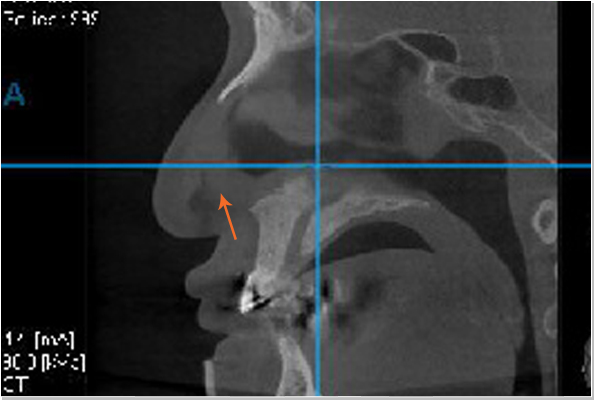

비중격만곡증 비정상

휘어있는 비중격